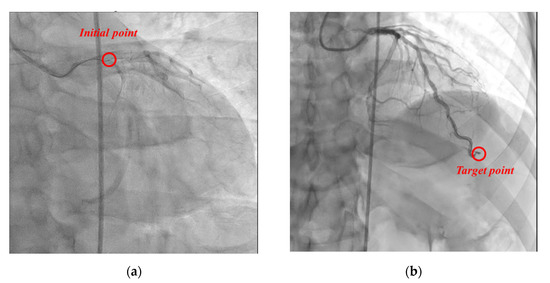

For efficacy evaluation, in the coronary angiography of the two subjects participating in this clinical trial, the guidewire was transferred to the target site of the coronary artery (subject 1: “left anterior descending artery”, subject 2: “right coronary artery”) using the proposed master–slave robotic system, without manual manipulation, as shown in Figure 18. At this time, there was no damage or dissection of the distal intima (“Coronary artery dissection—The National Heart, Lung and Blood Institute classification” criteria, evaluated as type A). Accordingly, coronary angiography using the proposed master–slave robotic system of the two subjects registered in this clinical trial was evaluated as a “technological success”.

Figure 18. Angiographic views of the left coronary artery of patient 1. (a) The guidewire was located at the entrance of coronary. (b) The guidewire was located at target point.

Biosensors 11 00329 g018